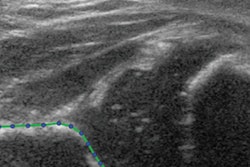

Image courtesy of Catherine Lebel, PhD.In addition, an analysis of structural connectivity on a network level showed that higher depression symptoms in mothers were associated with lower clustering and weaker local efficiency in the default mode network in babies born during the pandemic. This also aligned with pre-COVID-19 research findings, Lebel said.